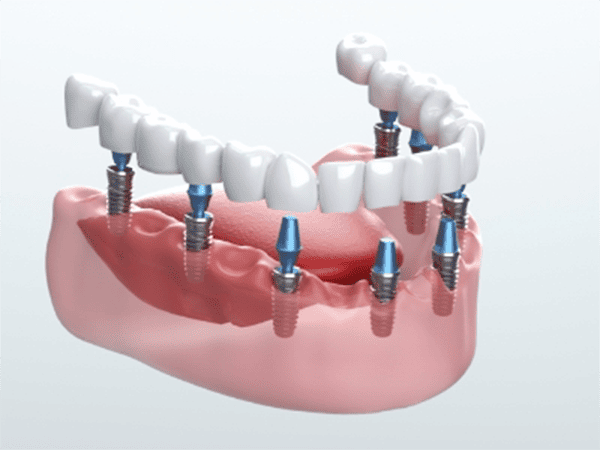

総入れ歯から解放される!1日で固定式の歯を取り戻す

当院のAll-on-4 / All-on-6なら解決できます

All-on-6料金 165万円(税込181.5万円)

■ おすすめのAll-on-6(片顎フルブリッジ)

165万円(税込 181.5万円)

• インプラント体(6本分の人工歯根の埋入)

• アバットメント(インプラントと歯を繋ぐ土台)

• 上部構造(最終的に装着する美しく丈夫な人工歯)